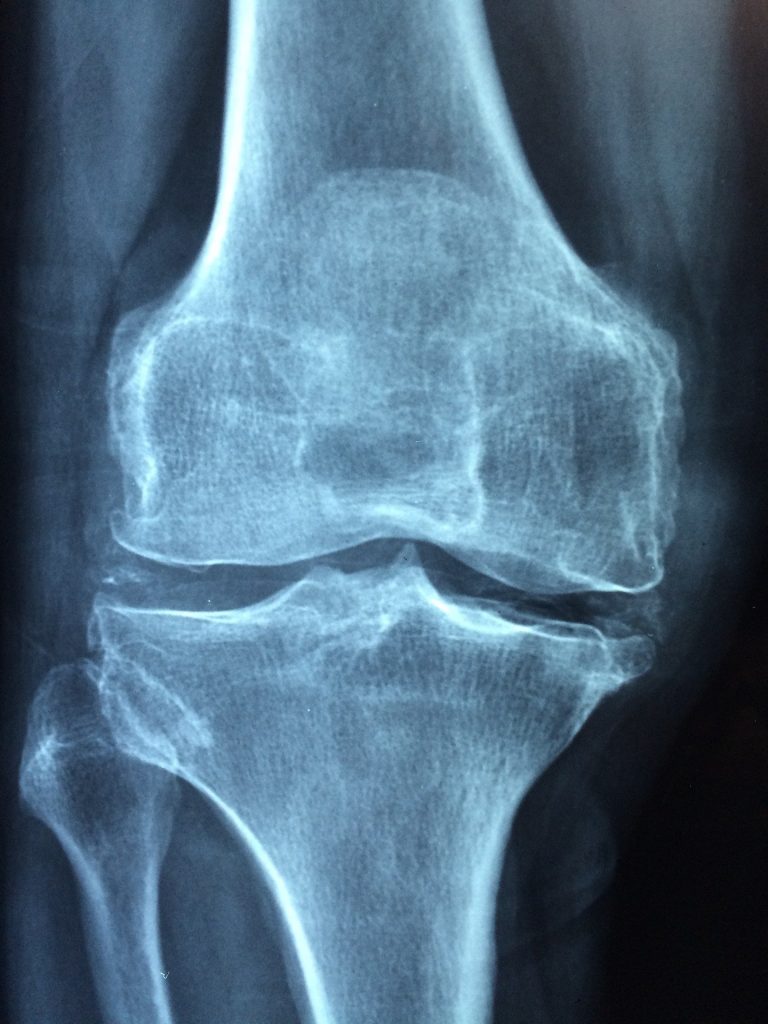

Arthritis comes in two main forms (although there are around 100 diagnosed types), the common version which affects individual joints is known as osteoarthritis, whereas the version which attacks the whole body all at once is rheumatoid arthritis.

In both cases there is a huge amount of inflammation around the area affected and a gradual wearing away of the bony surfaces of the joint.

Treatment involves a heavy dose of anti-inflammatory pain killers, steroid injections and ultimately surgery to replace the afflicted bones – knees & hips being the most regularly replaced joints due to this condition.